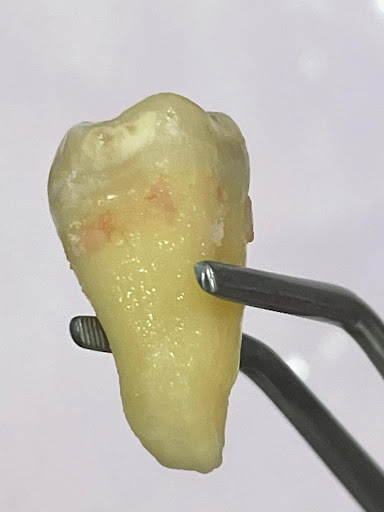

Photos

Photos of reviews